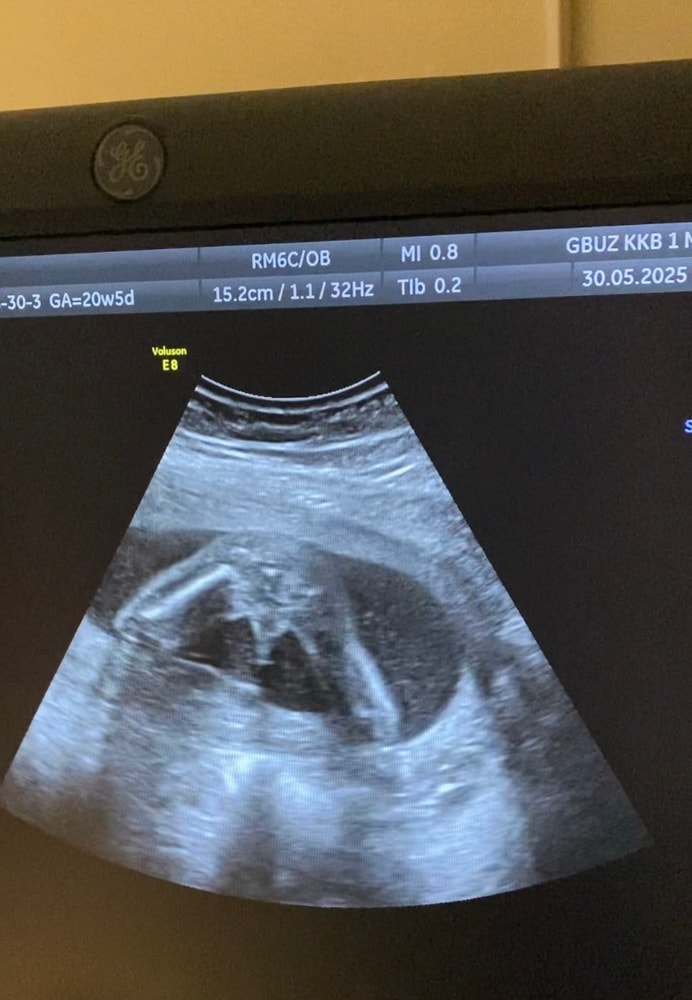

УЗИ, КТГ, доплерПоказала значит я фотки с узи своим подружкам мол ждем мальчика,а они мне начали говорить,что похоже на девочку больше.Либо с беременностью я стала более внушаемой,но теперь сомневаться начала и мой беременный мозг уже сносит🥲Врач четко показала на узи между ног,что есть 🔔🔔 и я четко видела.Еще раз приложу фотки узи,обвела что врач имела ввиду.Это ракурс как раз между ножек.Сказала у девочки не может так за контуры тела выходить.Короче,девочки кто разбирается в узи успокойте меня и мое любопытство.Хотели уже родных собирать пока тепло сообщать о внуке,а теперь во мне сомнение затесалось.Ну мальчик же,нет?Умоляю,не пишите про сдачу крови только.Если бы я знала,что так долго надо будет ждать и терпеть,то сдала бы уже на 10 неделе и не мучилась(